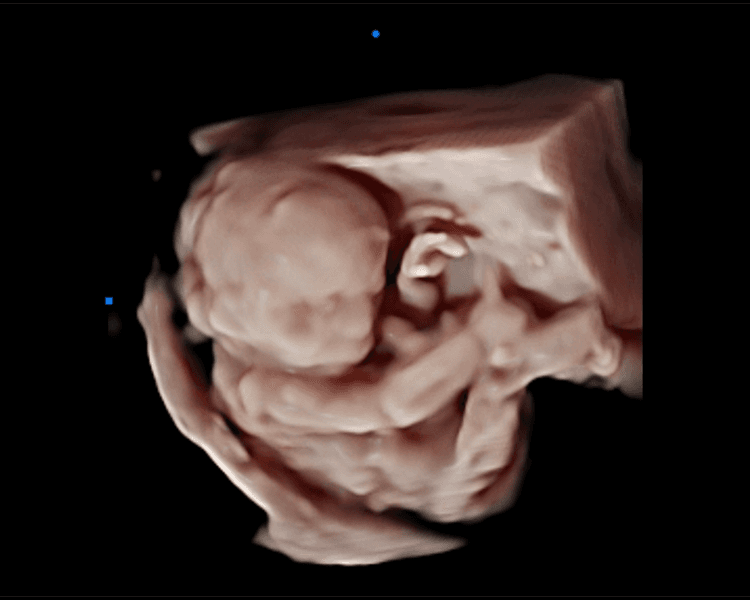

Ecografía Emocional 5D: Vive la Magia de Conocer a tu Bebé. En Ecolove ❤️, te invitamos a vivir una experiencia única y mágica con nuestra ecografía emocional 5D. Imagina ver a tu bebé en alta definición 3D y 5D, captando sus movimientos, gestos y hasta sus primeras sonrisas, todo con la calidad de una película de cine. 🎥 Es mucho más que una ecografía, es un momento lleno de amor, emoción y conexión. Un recuerdo eterno que podrás compartir con los que más quieres. 🤰🏻👨👩👦👦 ¡Reserva tu cita y deja que la magia del cine te acerque a tu bebé!